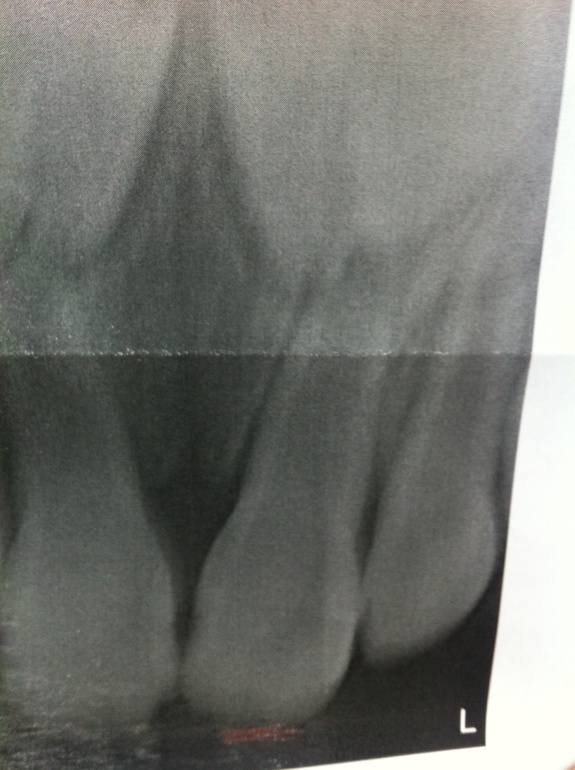

Зуб удалять никто не будет. Перелома-то корня нет.

Необходим пока контроль за зубом, он может посветлеть обратно. Через месяц опять нужен снимок. А уже после этого принимать решение- удалять нерв из зуба и пломбировать каналы или все миновало.